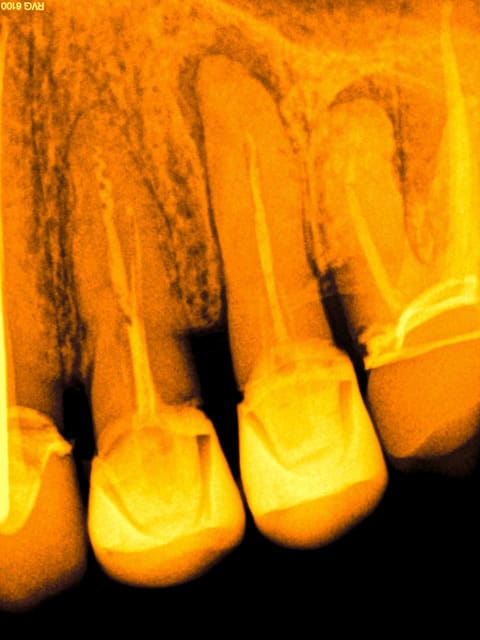

1 ikkzaa - Eugenol

2 nts546 - Eugenol

Aucune magie. SX, largo 3 sur double bague verte ( pour ouvrir les entrées hein) SX le plus loin possible ( entran), S1 (lime manuelle 10 si ca force) s1 (endomaster) , R25 (wd gold). J'ai mis des années à trouver cette séquence en passant par tous les systèmes possibles et imaginables.

Les butées sont chiantes à passer il est vrai.